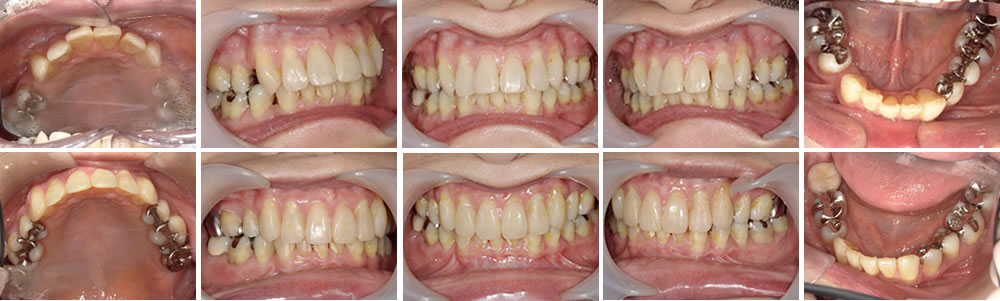

マウスピース矯正(インビザライン)で前歯の叢生を改善した症例

年齢

30代

性別

男性

症例を見る